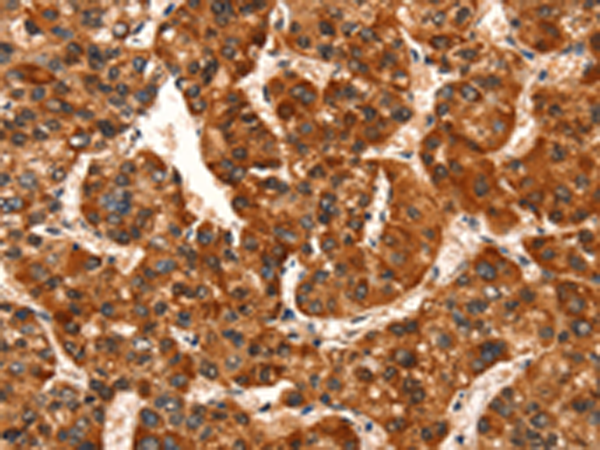

分类: 科研抗体货号: P11210别名:应用: IHC反应种属: Human, Mouse